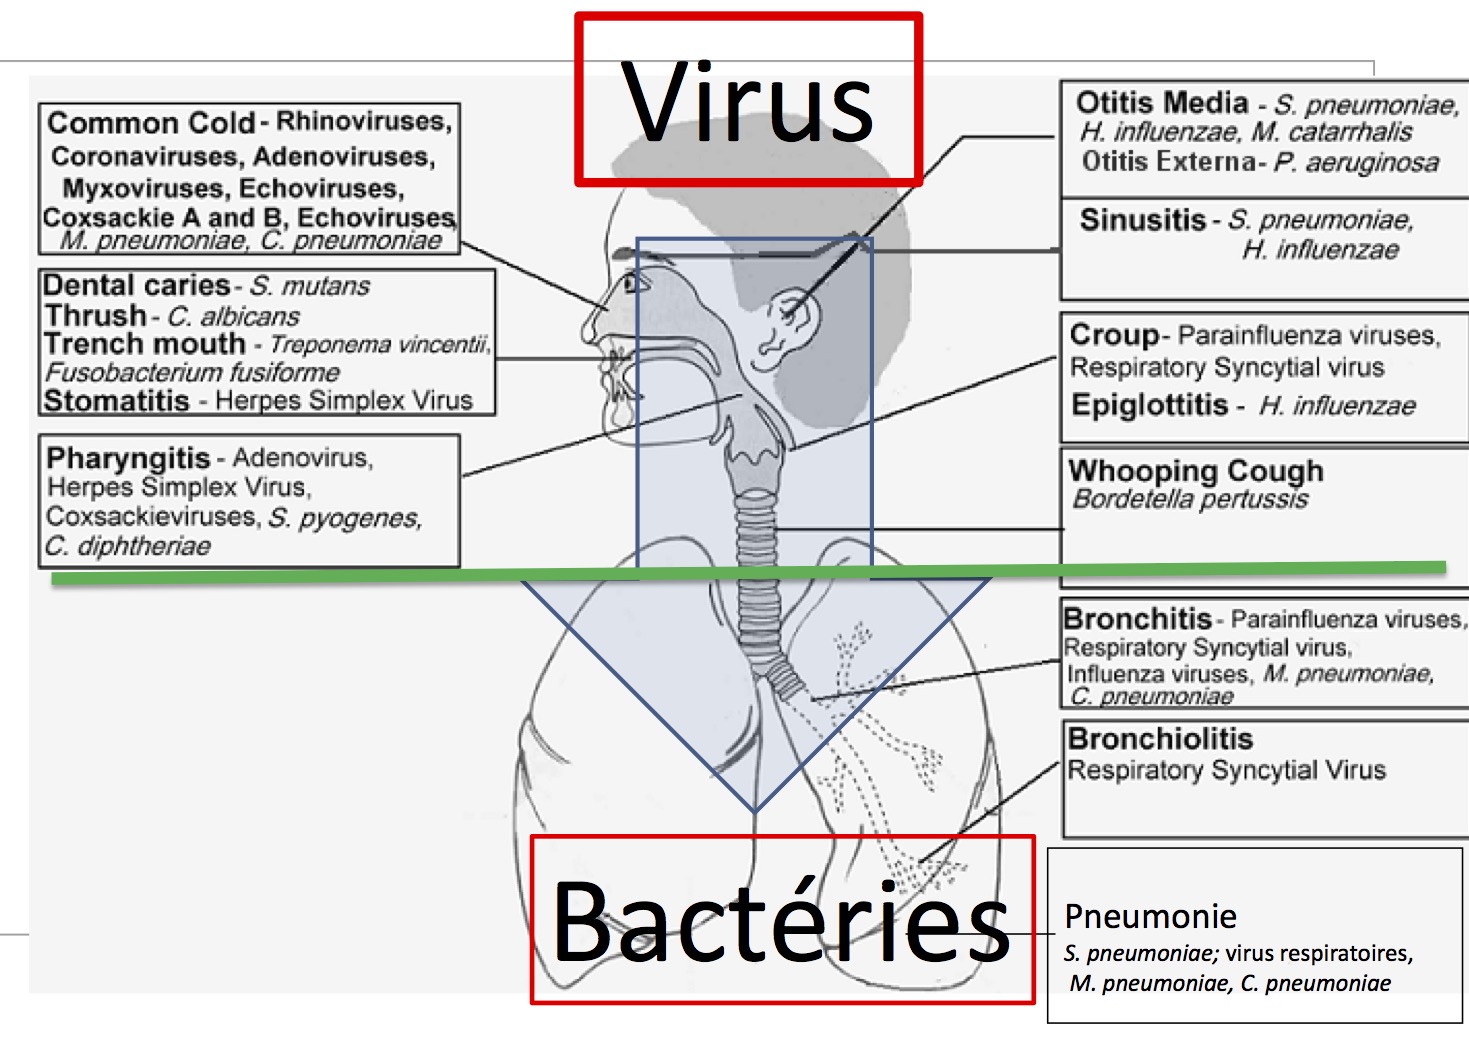

Infections of the respiratory tract are grouped according to their symptomatology and anatomic involvement. Acute upper respiratory infections (URI) include the common cold,.

Revue générale des infections virales respiratoires – L’étiologie, la physiopathologie, les symptômes, les signes, les diagnostics et les pronostics à partir des Manuels MSD,.

De nombreux agents pathogènes peuvent provoquer des infections des voies respiratoires. Bon nombre de ces infections produisent des signes et des symptômes similaires, mais.